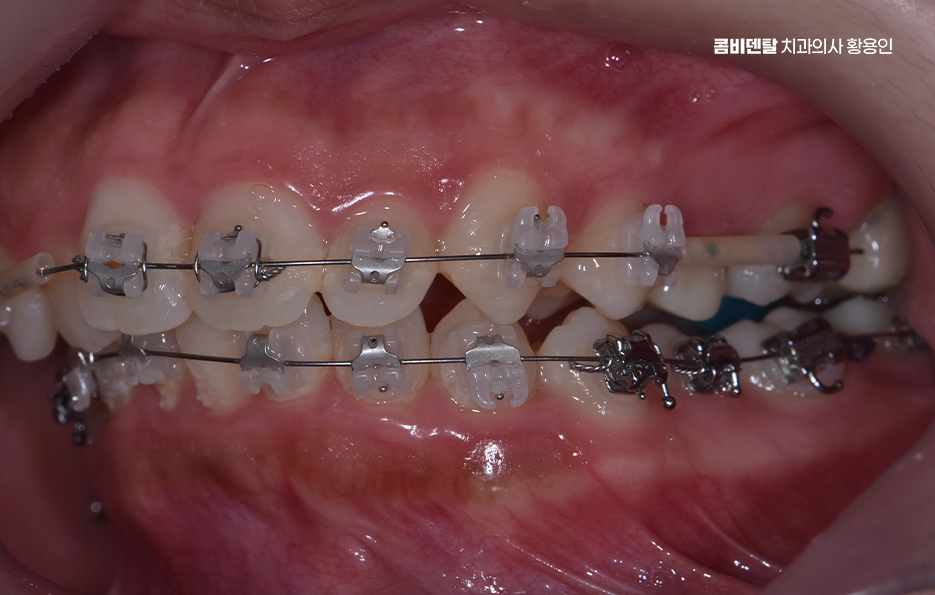

비발치 돌출입 교정 가능한 대표적인 케이스는 치아 배열의 공간이 비교적 충분한 경우로서 치아가 전체적으로 가지런하지는 않지만, 심하게 겹쳐 있지 않고 잇몸뼈 안에 어느 정도 여유 공간이 있는 경우에는 발치 없이도 치아를 뒤쪽으로 이동시키는 것이 가능한 경우가 있었어요.

치아 크기가 비교적 작거나, 턱의 크기에 비해 치아가 과도하게 크지 않은 경우도 비발치 돌출입 교정이 가능한 조건 중 하나로 같은 돌출입이라도 치아 크기와 턱뼈 크기의 비율에 따라 치료 접근이 달라지는데 치아가 상대적으로 작은 경우에는 공간을 확보하기가 더 수월하고 이런 경우에는 치아를 재배열하면서 자연스럽게 앞니 위치를 조정할 수 있었어요.

턱뼈의 위치와 형태도 중요한 기준이 되며 잇몸뼈 자체가 과도하게 앞으로 튀어나와 있는 골격성 돌출입의 경우에는 비발치 교정만으로는 한계가 있는 경우가 많은 반면 턱뼈의 위치는 비교적 정상 범위에 있고, 치아 배열로 인해 돌출이 강조되어 보이는 경우라면 비발치 교정이 현실적인 선택지가 될 수 있었어요.

비발치 돌출입 교정에서 주로 사용되는 방법 중 하나는 악궁 확장으로 치아가 나 있는 폭을 넓혀서 공간을 확보한 뒤, 치아를 재배열하는 방식인데 이 방법은 공간을 만들어 발치 없이 교정을 진행할 수 있다는 장점이 있지만, 무리한 확장은 잇몸이나 치아 뿌리에 부담을 줄 수 있기 때문에 한계 범위 안에서만 적용되고 있어요